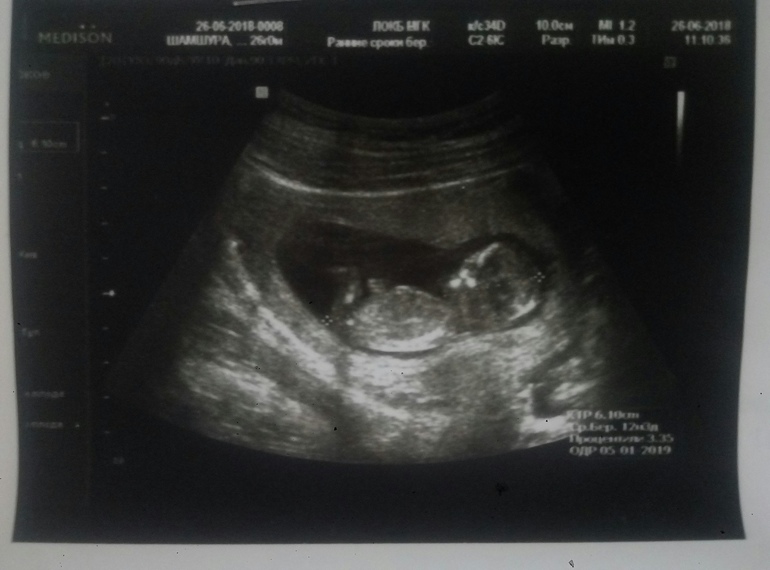

А вот и мы))))1-ый скриниг)

Сегодня я познакомилась с нашим маленьким пузанчиком))) Все хорошо, патологии исключили) Наконец-то пришло осознание того, что внутри меня растет новая жизнь) Дату родов назначили на 4 января))) Вот такой подарочек на Новый год и мужу на день рождения))))) Растем дальше)